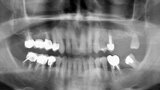

Rehabilitace unilaterální maxilární bezzubosti